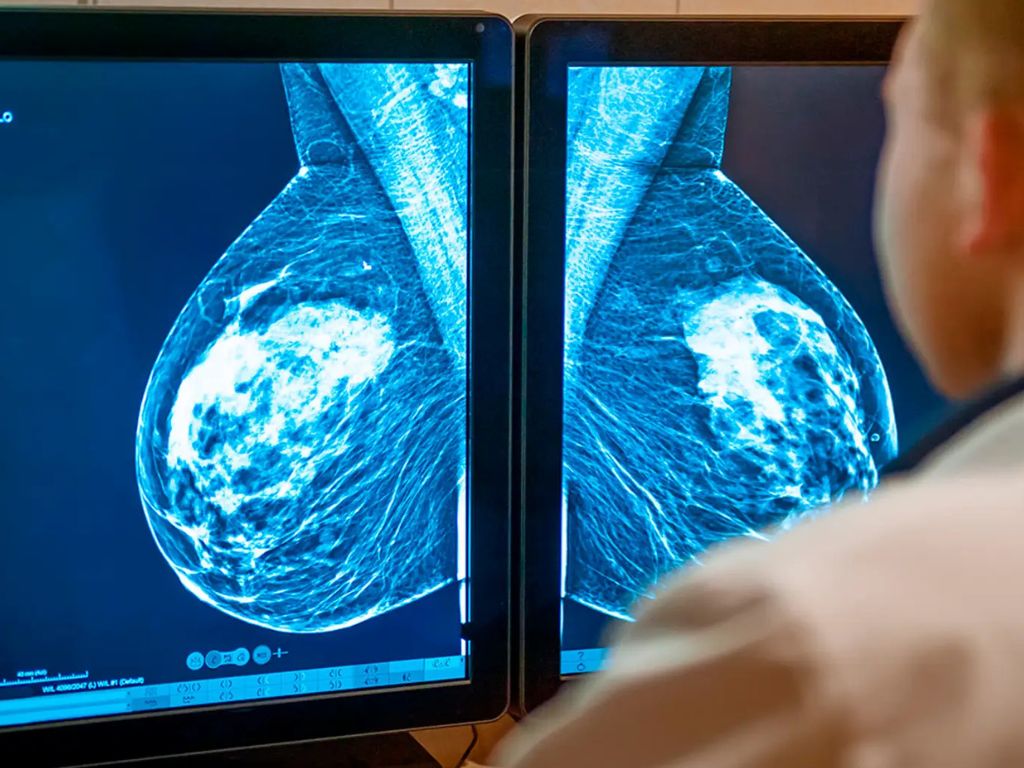

Cáncer de mama triple negativo: dianas terapéuticas y decisión clínica

El cáncer de mama triple negativo (TNBC) representa ~10–15% de los tumores mamarios y se caracteriza por ausencia de RE/RP y de amplificación de HER2. Es biológicamente heterogéneo y con mayor agresividad clínica.